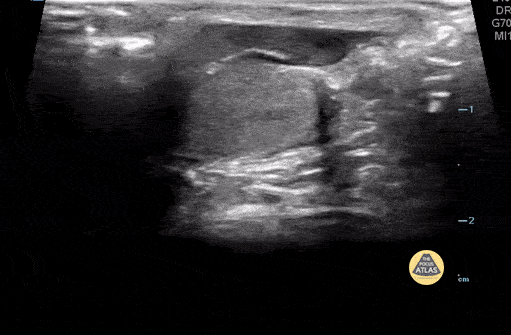

2 yo male present with testicle pain and swelling. POCUS shows torsion of the appendix of the testicle. Please note hyperechoic appendage of testicle. Contributor: Paul Khalil, MD, Nicklaus Children's Hospital, @khalil3paul